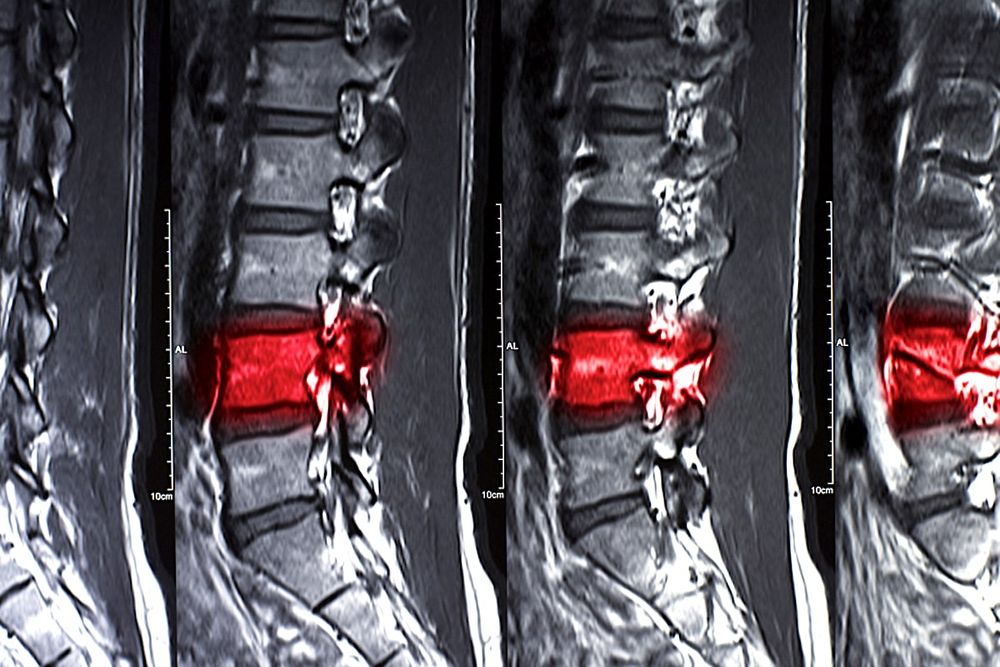

Réparer la moelle épinière en utilisant les cellules souches des patients

Plusieurs équipes de chercheurs à travers le monde sont sur le point d'accomplir ce qui semblait impossible il y a seulement quelques années... Récemment par exemple, en injectant des cellules souches de moelle osseuse (MSC) chez des patients atteints de lésions de la moelle épinière, des chercheurs de l'université de Yale et de Sapporo (Japon) ont obtenu des résultats très encourageants, constatant une amélioration significative de leurs fonctions motrices.

Une amélioration neurologique a été constatée chez 12 des 13 patients, six mois après la perfusion de MSC. Cependant, un gain fonctionnel léger a été observé seulement un jour après la perfusion chez cinq des patients. L'amélioration de la structure de la moelle épinière a été elle aussi rapide, notable déjà un mois après le traitement.